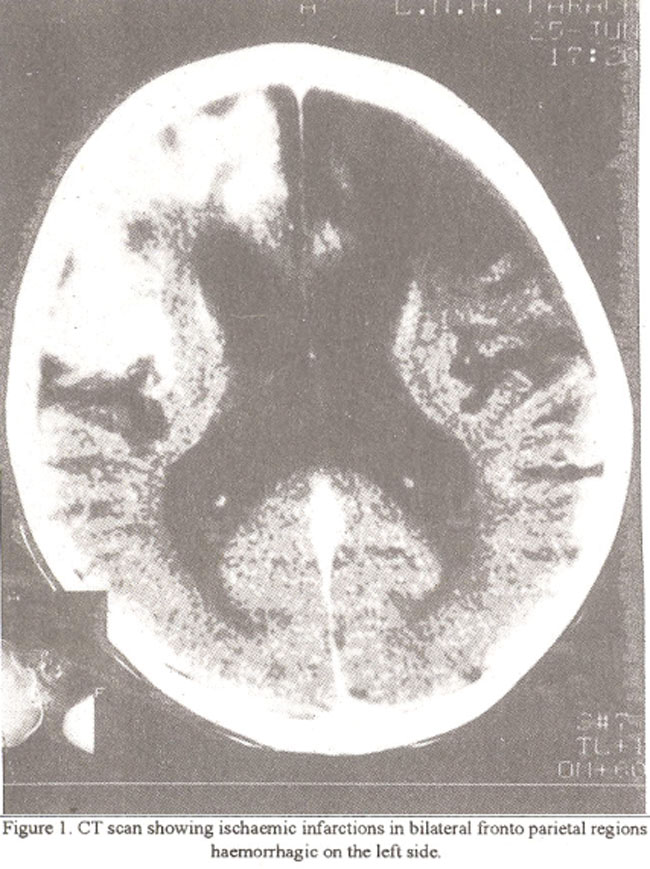

The CT scans and MRI imaging findings were reviewed for signs of infarctions, hemorrhages, atrophy, ventricular size, visualization of circle of Willis and Moya Moya vessels. Angiographic findings were reviewed for Steno-occlusive disease involving the internal carotid, anterior cerebral, middle cerebral and posteriorcerebral vessels, presence of dilated tortuous vessels at basal ganglia (Moya Moya vessels), evidence of medullary arteries, evidence of collaterals through branches of middle meningeal vessels and ophthalmic artery and for presence of aneurysms. Infarctions in bilateral cerebral hemispheres were present in all patients who had CT scan or MRI (Figure 1).

Atrophy and ventricular dilatation was moderate in two patients and mild in one patient. Moya Moya vessels were seen on CT scan only in one patient (Figure 2).